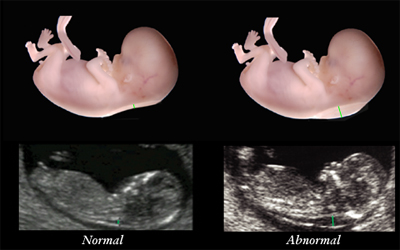

1) Υπερηχογράφημα κύησης και μέτρηση αυχενικής διαφάνειας: Είναι ένα υπερηχογράφημα στο οποίο προσδιορίζονται σοβαρές ανατομικές ανωμαλίες και μετριέται και η αυχενική διαφάνεια ( το πάχος του ιστού πάνω από τον αυχένα του εμβρύου). Η μέτρηση δείχνει την πιθανότητα για σύνδρομο Down καθώς και για άλλες χρωμοσωμικές ανωμαλίες.

1) Υπερηχογράφημα β’ επιπέδου (ΕΚΤΕΛΕΙΤΑΙ ΑΠΟ ΕΞΕΙΔΙΚΕΥΜΕΝΟ ΣΤΗΝ ΕΜΒΡΥΟΜΕΤΡΙΚΗ ΙΑΤΡΙΚΗ ΙΑΤΡΟ): Είναι ένας υπέρηχος που εξετάζει με κάθε λεπτομέρεια την ανατομία του εμβρύου. Ελέγχεται εκ νέου η στατιστική πιθανότητα για κίνδυνο χρωμοσωμικών ανωμαλιών.